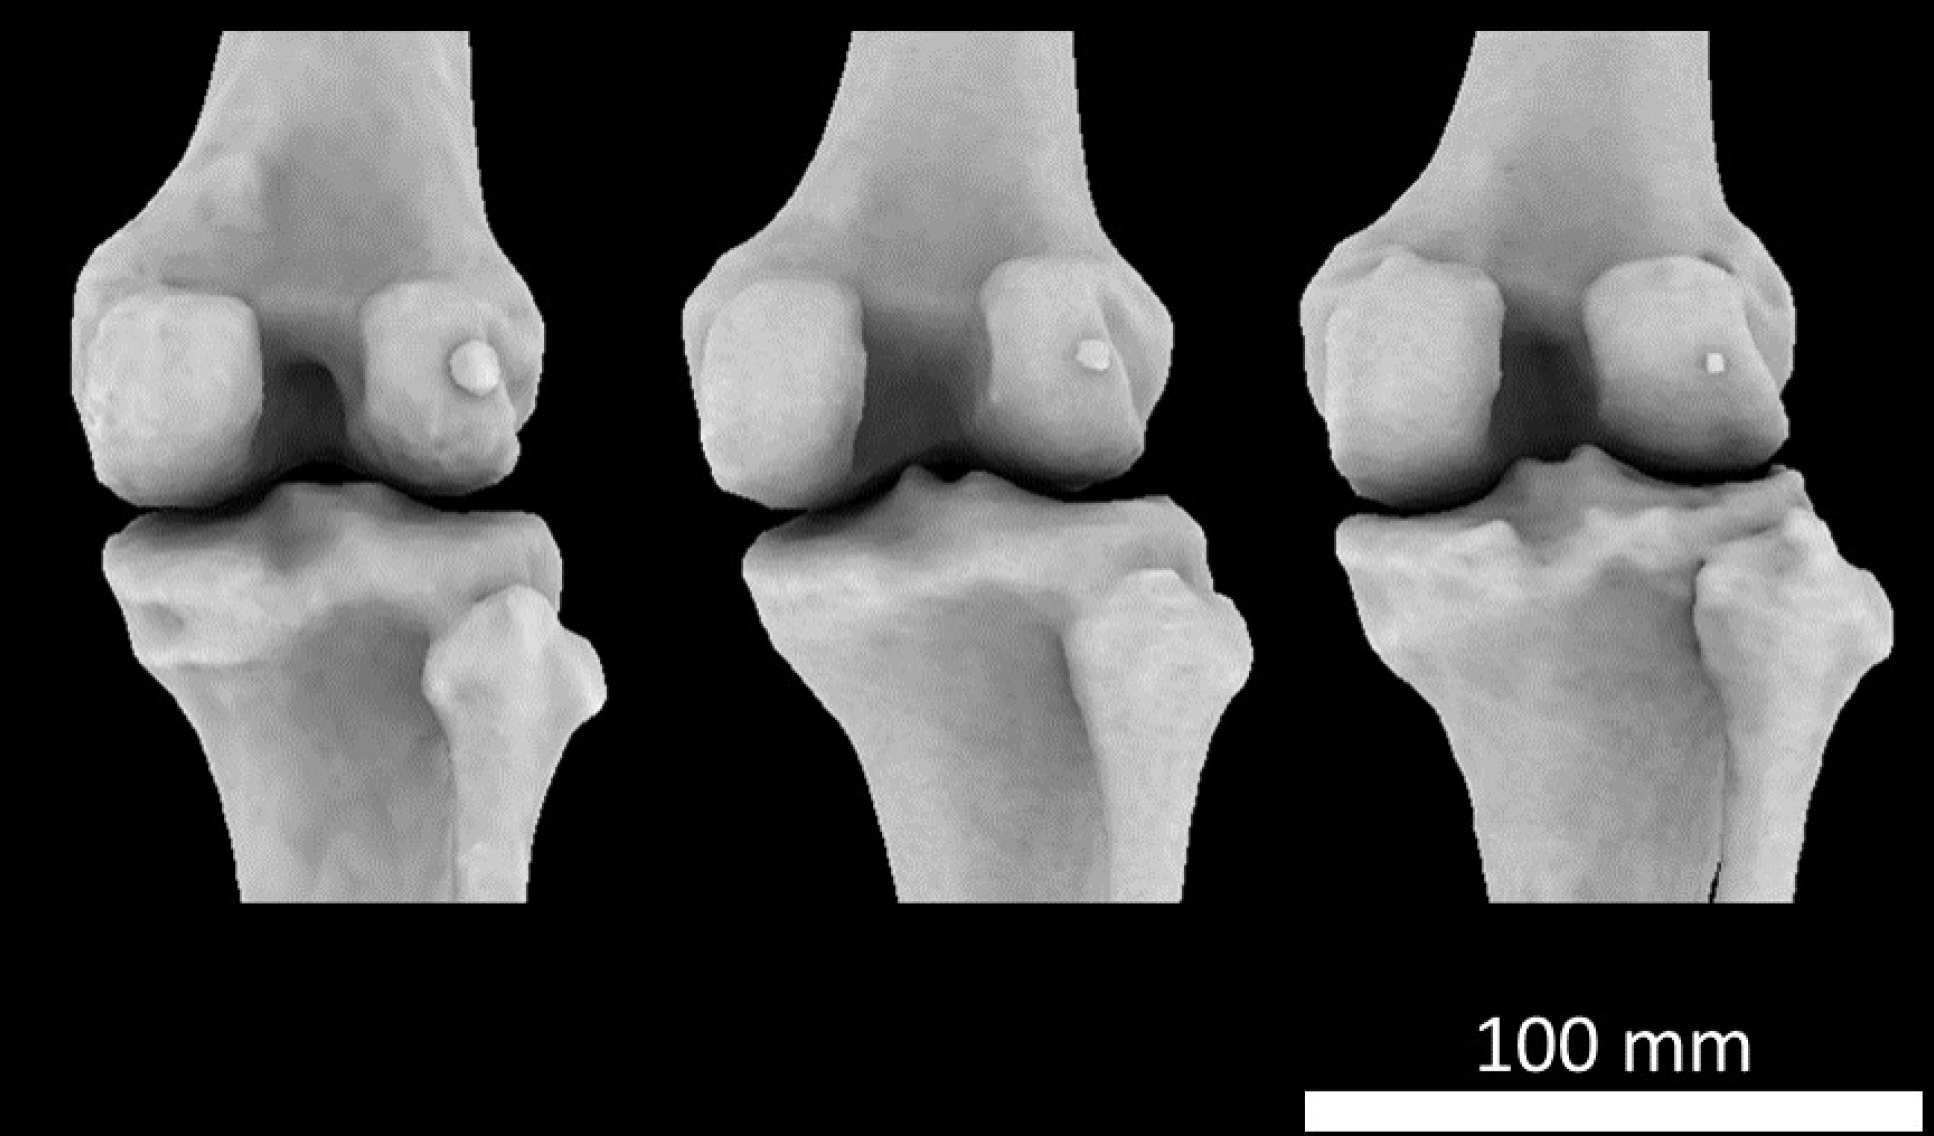

CT scan of a knee joint with fabella

The tiny fabella bone is found in a knee joint tendon

Dr Berthaume added: “The average human, today, is better nourished, meaning we are taller and heavier. This came with longer shinbones and larger calf muscles – changes which both put the knee under increasing pressure. This could explain why fabellae are more common now than they once were.”CT scan of knee joints with fabellaeNot all people have fabellae, however, and there is likely a genetic component controlling the ability to form one – but for those who can form a fabella, this increased mechanical forces might drive their formation.